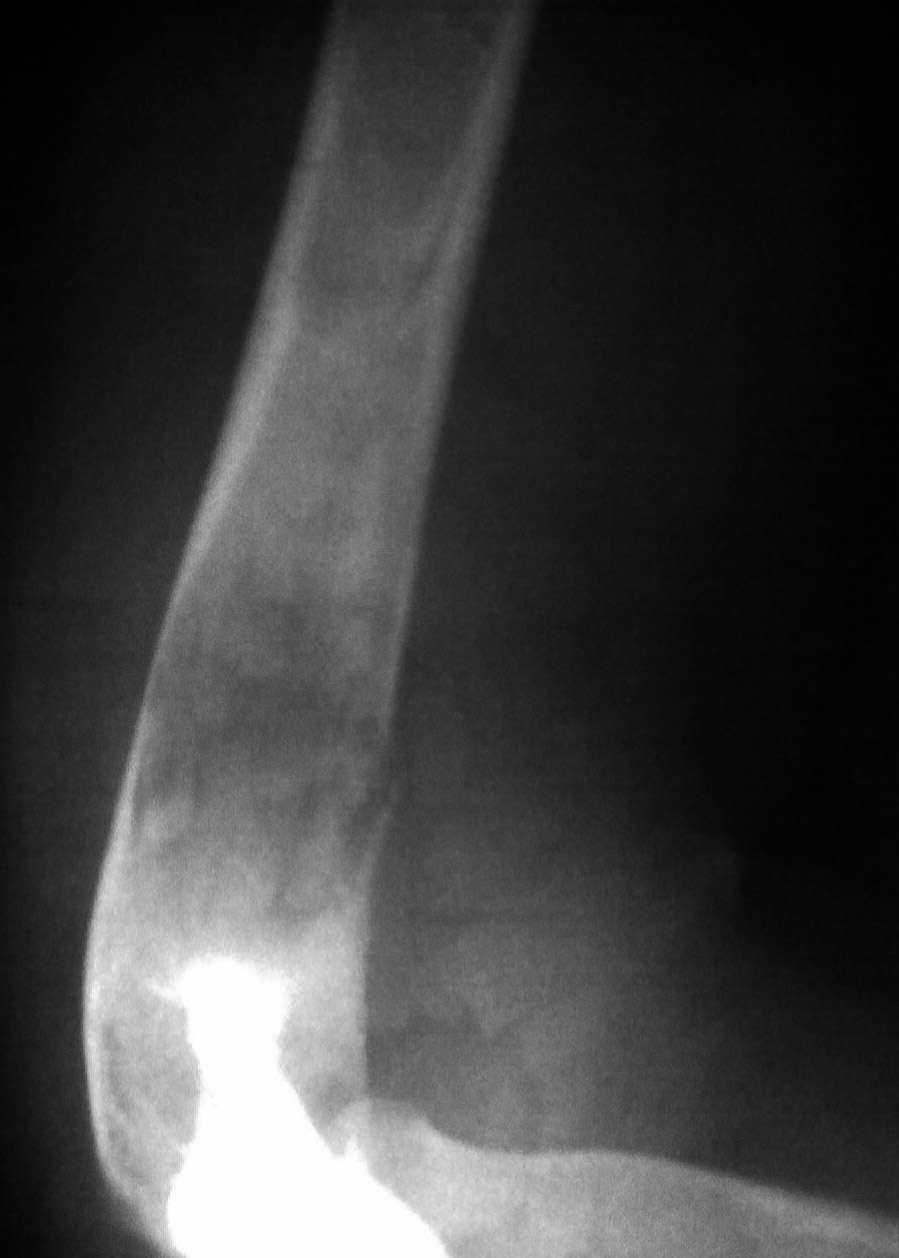

标题: CT17838:F20Y,右肱骨痛疼一年余 [打印本页]

标题: CT17838:F20Y,右肱骨痛疼一年余

右肱骨中下段恶性肿瘤(纤维肉瘤可能性大)伴病理性骨折。

中央型纤维肉瘤主要破坏松质骨,x线表现以局灶性透亮区为主,其中无成骨现象。边缘参差不齐。中间偶可有散在小钙化点,邻近骨皮质局限变薄,轻度膨胀,虽常被穿破,然多无骨膜反应,有些病例,病变范围较广,骨小梁排列紊乱夹杂有骨质破坏的小斑点状透光区,分布弥散,偶有少量骨膜新骨形成。周围型肿瘤常位于软组织中,呈圆形或卵圆形阴影,密度较肌肉影略离,肿块中可出现少量均匀钙化点。

发病率低,至少比骨肉瘤的发病率低10倍。无明显性别差异,或仅轻微偏重于男性。可发生在任何年龄段,在15~60岁之间的分布没有什么差别,发生在青春期前为个别病例。

好发于以下部位,按顺序排列为股骨远端、胫骨近端、股骨近端、肱骨近端及骨盆,约50%的病例发生在膝关节周围,20%在四肢骨近端,20%在躯干骨,很少在手足骨。

在长骨,一般位于到骨干的一端或干骺端;在成人常侵及骨骺,纯粹定位于骨干者少见。

疼痛是主要症状。在低度恶性的纤维肉瘤中,肿胀轻且晚,有时无肿胀,但当纤维肉瘤侵袭性较强时,肿胀则较早出现。纤维肉瘤的病理性骨折多见。